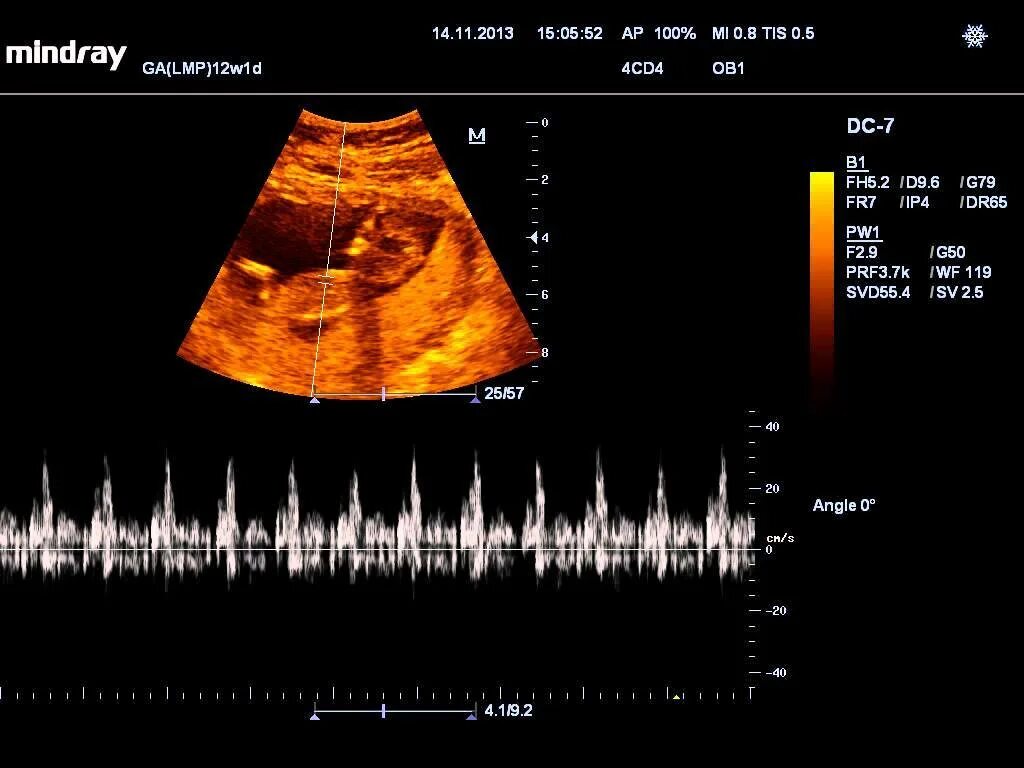

На какой недели бьется сердце плода